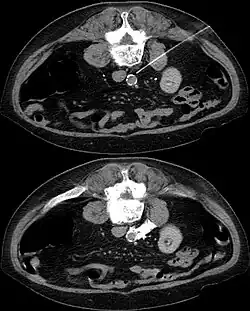

- Ausschaltung der Ganglien durch Injektion von Alkohol oder Phenol gemischt mit einem örtlichen Betäubungsmittel. Die Lage der Nadel wird durch computertomographische Aufnahmen überwacht. Unerwünschte Wirkungen sind ähnlich wie bei den operativen Eingriffen, allerdings seltener. Komplikationen werden mit ca. 2 % angegeben, Symptombesserung mit 38–32 %.

- Auch an anderen Stellen des Körpers kann das sympathische Nervengeflecht blockiert werden. Der an den großen Bauchgefäßen liegende sympathische Plexus kann z. B. in örtlicher Betäubung unter Steuerung im Computertomogramm durch Injektion von konzentriertem Alkohol ausgeschaltet werden (Verfahren der interventionellen Radiologie).